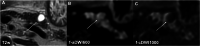

Methods: Eighty-two patients with known or suspected IPMN were retrospectively enrolled. Computed high-b-value images at b = 1000 s/mm2 were calculated from standard (b = 0, 50, 300, and 600 s/mm2) DWI images for conventional full field-of-view (fFOV, 3 × 3 × 4 mm3 voxel size) DWI. A subset of 39 patients received additional high-resolution reduced-field-of-view (rFOV, 2.5 × 2.5 × 3 mm3 voxel size) DWI. In this cohort, rFOV cDWI was compared against fFOV cDWI additionally. Two experienced radiologists evaluated (Likert scale 1-4) image quality (overall image quality, lesion detection and delineation, fluid suppression within the lesion). In addition, quantitative image parameters (apparent signal-to-noise ratio (aSNR), apparent contrast-to-noise ratio (aCNR), contrast ratio (CR)) were assessed. Diagnostic confidence regarding the presence/absence of diffusion-restricted solid nodules was assessed in an additional reader study.

Results: High-b-value cDWI at b = 1000 s/mm2 outperformed acquired DWI at b = 600 s/mm2 regarding lesion detection, fluid suppression, aCNR, CR, and lesion classification (p = < .001-.002). Comparing cDWI from fFOV and rFOV revealed higher image quality in high-resolution rFOV-DWI compared to conventional fFOV-DWI (p ≤ .001-.018). High-b-value cDWI images were rated non-inferior to directly acquired high-b-value DWI images (p = .095-.655).